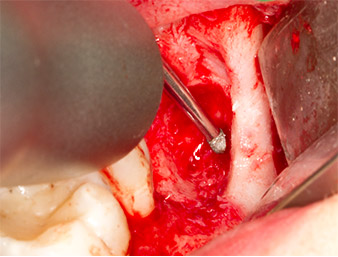

Nach Leitungs- und Lokalanästhesie wurde das Operationsfeld für einen bukkal-retromolaren Zugang weichgewebig eröffnet und dargestellt (Abb. 3).